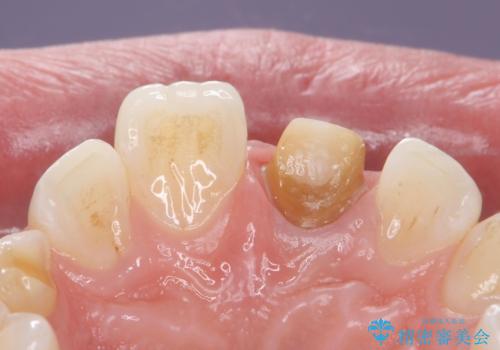

変色した前歯 ジルコニアクラウンでの修復

- 前歯の変色を主訴に来院された患者様です。

根管治療からのやり直しをした後、ジルコニアクラウンで色調の改善をしていきます。

- 左上1:根管治療(リトリートメント・前歯)/99,000円 ファイバーコア/22,000円 仮歯/11,000円 ジルコニアクラウン(スタンダード)/121,000円 合計253,000円費用は治療当時の料金となります

歯の黒ずみを完全に見えなくすることができ、大変喜んでいただけました。

被せ物を装着する際は、歯の中(根管)から綺麗にすることも重要となります。